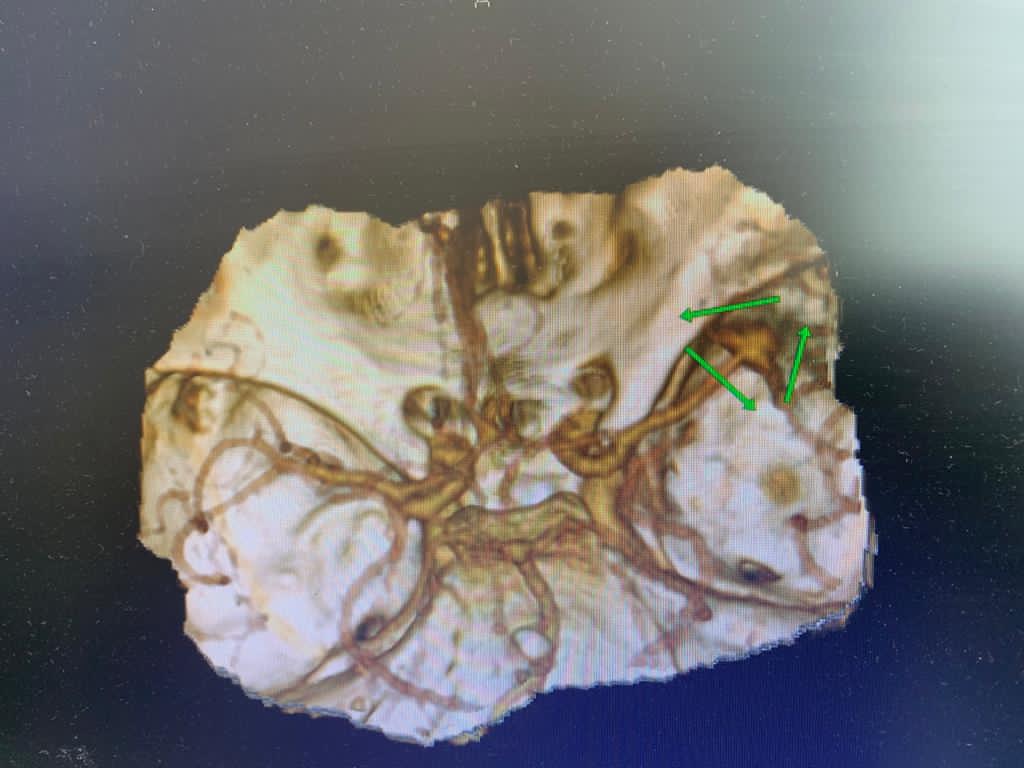

После проведённого обследования был поставлен диагноз: разорвавшаяся мешотчатая аневризма средней мозговой артерии. Опасностью при этом заболевании является высокий риск повторного кровоизлияния, что может привести к летальному исходу.

Послеоперационный контроль- аневризма выключена из кровотока полностью, все сосуды проходимы.